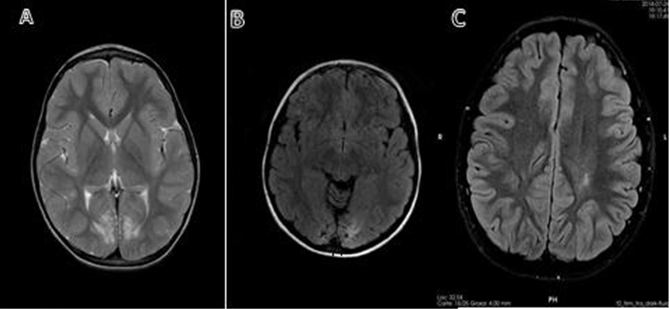

Neuroradiological findings on MRI: Patient #1 presents cortical atrophy-occipital lobes. Patient #2 with findings of hypogenesis of the corpus callosum without lesions due to hypoglycemia and of note also course with altered VEP pattern. Patient #3 with findings of bilateral frontal asymmetry with dysmorphic appearance of the zonal gyri in relation to probable bilateral frontal polymicrogyria. No evidence of occipital gliosis suggestive of perinatal hypoglycemia injury. Patient #6 with findings of subtle bilateral posterior occipital subcortical subcortical white matter lesion, topography at the level of the optic radiations. Patient #10 presence of leukoencephalopathic lesions in both parietooccipital regions. Patient #11 chronic gliotic lesions affecting peri-ventricular and deep white matter, standing out at the level of both the frontal lobes, centroemiovial regions as well as periartrial and periventricular regions of left predominance (Table 4 & Figure 1).

Figure 1

A) Patient #1. MRI in T2, axial slice, bilateral occipital atrophy with white matter involvement.

B) Patient #10. MRI in FLAIR, axial cut, occipital atrophy on both sides.

C) Patient #11 MRI in FLAIR, axial section, chronic gliotic lesions affecting periventricular and deep white matter, standing out at the level of central semi-oval regions, predominantly left.